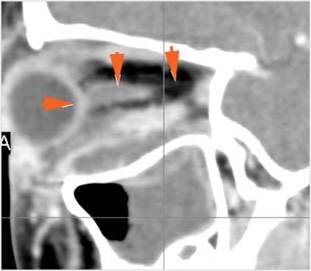

Nasal Cavity and Nasolacrimal Drainage System

There is mucoperiosteal thickening in the nasal cavity. [Yes/No]

There is ulceration or erosion of the nasal septum or turbinates. [Yes/No]

There is mucosal thickening of the posterior lateral walls of the nasal cavity, cribriform plate or the face of the sphenoid bone. [Yes/No]

There is infiltration of the fat surrounding the nasolacrimal sac. [Yes/No]

There is infiltration of soft tissues or bone erosion along the nasolacrimal fossa or canal. [Yes/No]